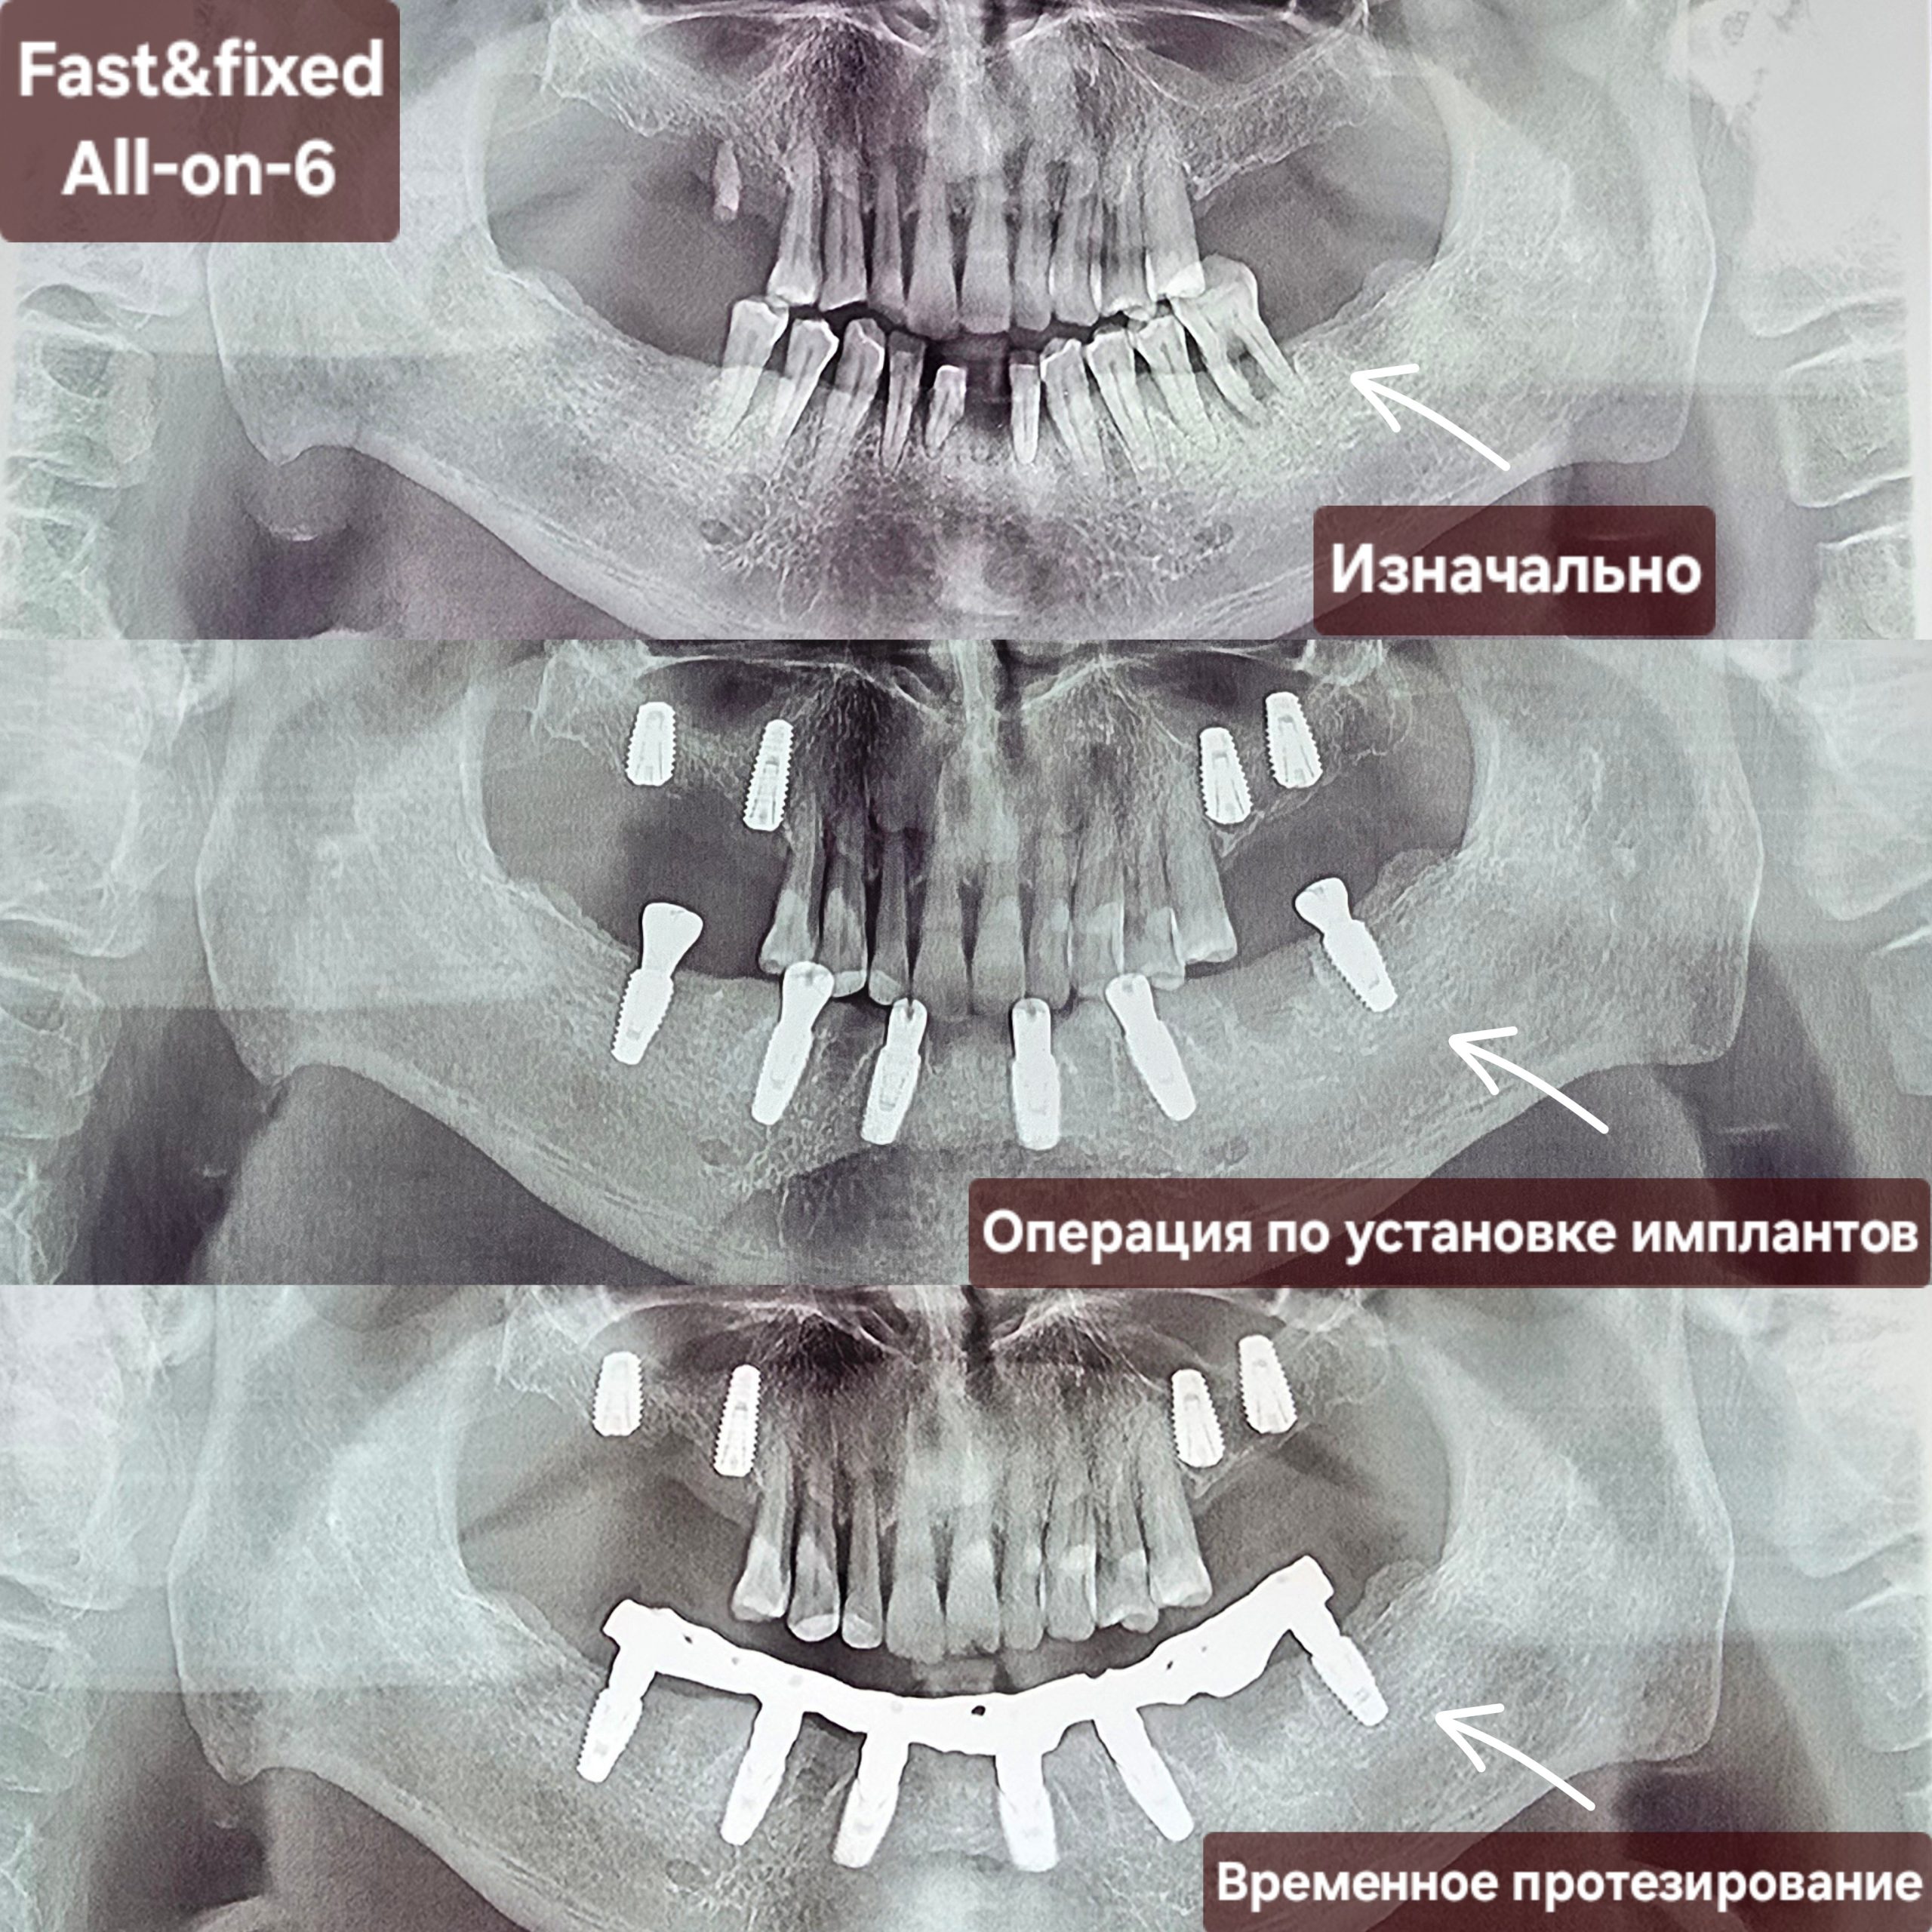

Этапы полной реабилитации с использованием методики All-on-X.

Хирургическое вмешательство

Следующий этап включает в себя установку зубных имплантатов в челюстную кость. При необходимости проводится удаление зубов, и кость подготавливается к установке имплантатов. В зависимости от плотности костной ткани пациента и общего состояния полости рта, на каждую челюсть может быть установлено от четырех до восьми зубных имплантатов. Имплантаты размещаются под углами, рассчитанными на обеспечение максимальной стабильности и поддержки протеза, а также равномерного распределения окклюзионных нагрузок.

Фиксация временного протеза

После операции по установки имплантата будет зафиксирована временный фиксированный протез. Это одно из главных преимуществ техники All-on-X, поскольку пациенты получают немедленное эстетическое решение, и уже через несколько дней смогут наслаждаться новой улыбкой. Помимо эстетических преимуществ, временный протез также способствует восстановлению жевательной функции.